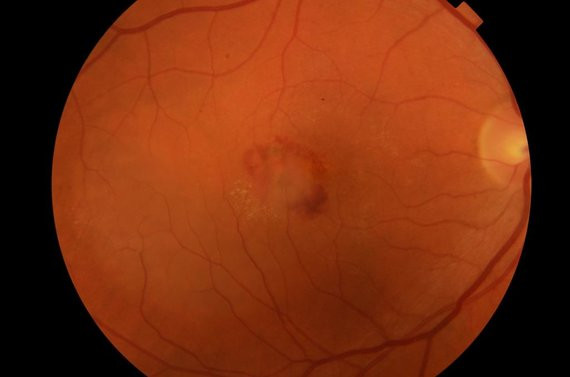

Diabetinė retinopatija

Diabetine retinopatija sergantys pacientai turi padidėjusį tinklainės kraujagyslių pralaidumą. Kapiliarai tinklainėje deformuojasi, užanka, susidaro naujos, nepilnavertės kraujagyslės iš kurių kraujuoja, vystosi negrįžtami tinklainės pokyčiai.

Geltonosios dėmės regeneracija

Už tai, kad matome – galime skaityti, skirti veidus, įverti siūlą į adatą – atsakinga geltonoji dėmė. Ji yra akies dugne, tai maždaug pusantro-dviejų milimetrų dydžio duobutė. Su amžiumi kyla amžinės geltonosios dėmės degeneracijos rizika. Kaip tuomet matome? Vaizde atsiranda dėmė pačiame centre.

Kaip pasitikrinti ar ši liga nesikėsina į jūsų akis? A. Makselis pataria pasiimti sąsiuvinį langeliais, kažkur centre pasidėti juodą tašką ir į jį įsižiūrėti iš skaitymo atstumo. Jei kažkur matyti vaizdo iškraipymai, linijos banguoja, nedelsiant reikėtų kreiptis į medikus. Daugelyje poliklinikų atliekamas minutės trukmės geltonosios dėmės būklės tyrimas – tad pasitikrinti galima labai greitai. Geltonosios dėmės degeneracija būna „sausoji“ ir „šlapioji“. Sausosios atveju nėra taip pavojinga, progresavimas labai lėtas, įtakos matymui – mažai. Šlapiosios atveju formuojasi naujos nepilnavertės kraujagyslės, iš jų sunkiasi skystis, ardantis normalią tinklainės struktūrą dėl ko ir atsiranda juodos dėmės vaizde, į kurį žiūrime tiesiai. Šoninis matymas visuomet lieka – tai vienintelė paguoda.

Kaip geltonosios dėmės degeneracija yra gydoma?

Degeneraciją stabdantys vaistai leidžiami tiesiai į akį. Gydymas labai brangus, viena injekcija kainuoja apie 1000 eurų. Valstybė šį gydymą kompensuoja. Siekiant sustabdyti ligos progresavimą, leidžiamos maždaug 6 injekcijos per metus. Prie abiejų ligos formų rekomenduojami maisto papildai skirti akims, kuriuose pagrindas yra liuteinas, zeaksantinas, vitaminai C, E, beta-karotinas. Vaistai sumažina su amžiumi susijusios geltonosios dėmės regeneracijos riziką, jos progresavimą, tačiau visiškai ligos neišgydo.